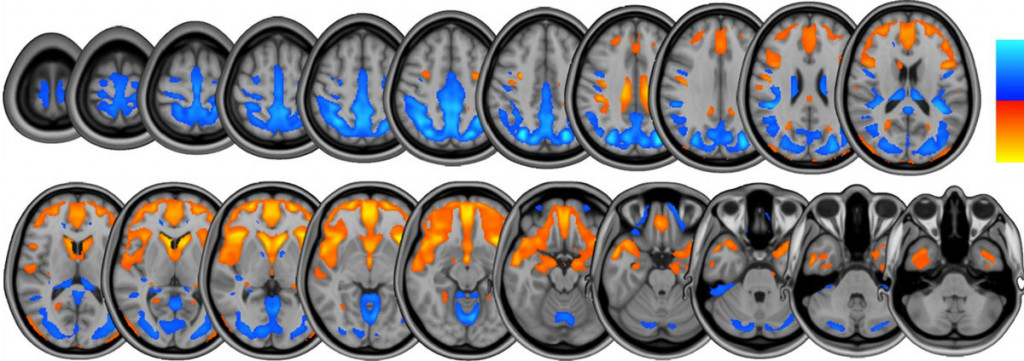

Temuan ini disampaikan oleh NASA dalam sebuah artikel di situs resminya. Dalam artikel tersebut, NASA telah beberapa kali meneliti kondisi otak para astronot di ISS. Hasilnya, kemampuan otak mereka ternyata menurun ketika kembali dari luar angkasa.

Menurut NASA, hal tersebut dikarenakan lingkungan ISS yang tanpa gravitasi sehingga memaksa bagian otak yang memproses pandangan tiga dimensi berhenti bekerja. Ini adalah masalah sekaligus tantangan baru bagi NASA yang ingin mendaratkan manusia di Mars beberapa tahun mendatang.